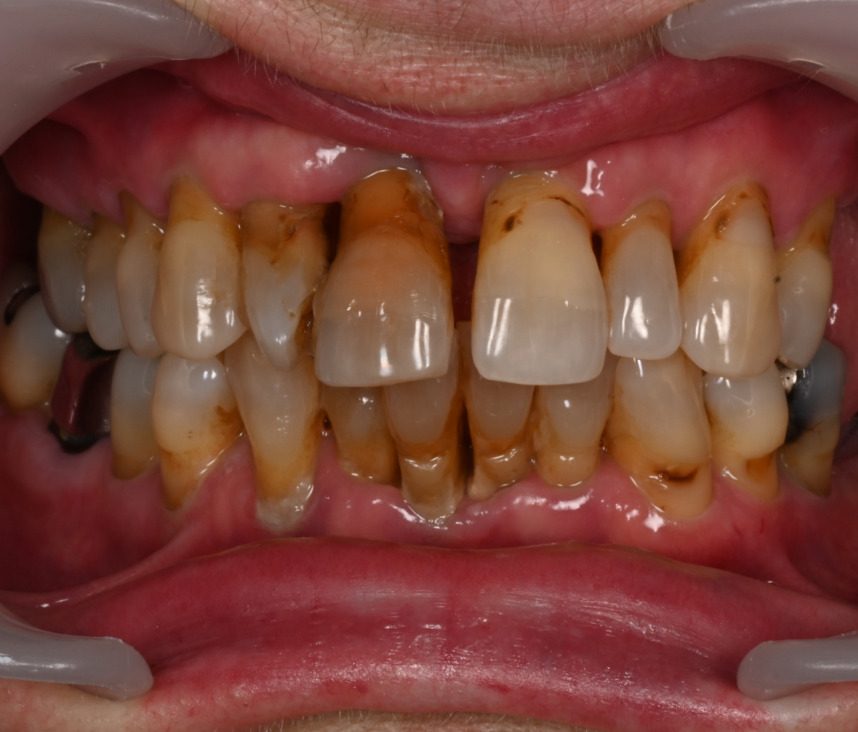

Cas cliniques

Que vous souffriez de problèmes d’occlusion, de perte de dents, de maladie parodontale, ou d’autres problèmes dentaires, une réhabilitation globale pourrait être la solution pour vous. Au cabinet dentaire du Docteur Malthieu à Amiens, nous sommes fiers de pouvoir proposer cette approche intégrée à nos patients.

La réhabilitation globale est une solution complète pour ceux qui ont des problèmes de santé bucco-dentaire multiples et complexes. Elle consiste en un plan de traitement personnalisé, conçu pour traiter toutes les affections dentaires en une seule fois. Cette approche globale permet de restaurer l’harmonie du sourire, tout en améliorant la santé bucco-dentaire de façon durable.